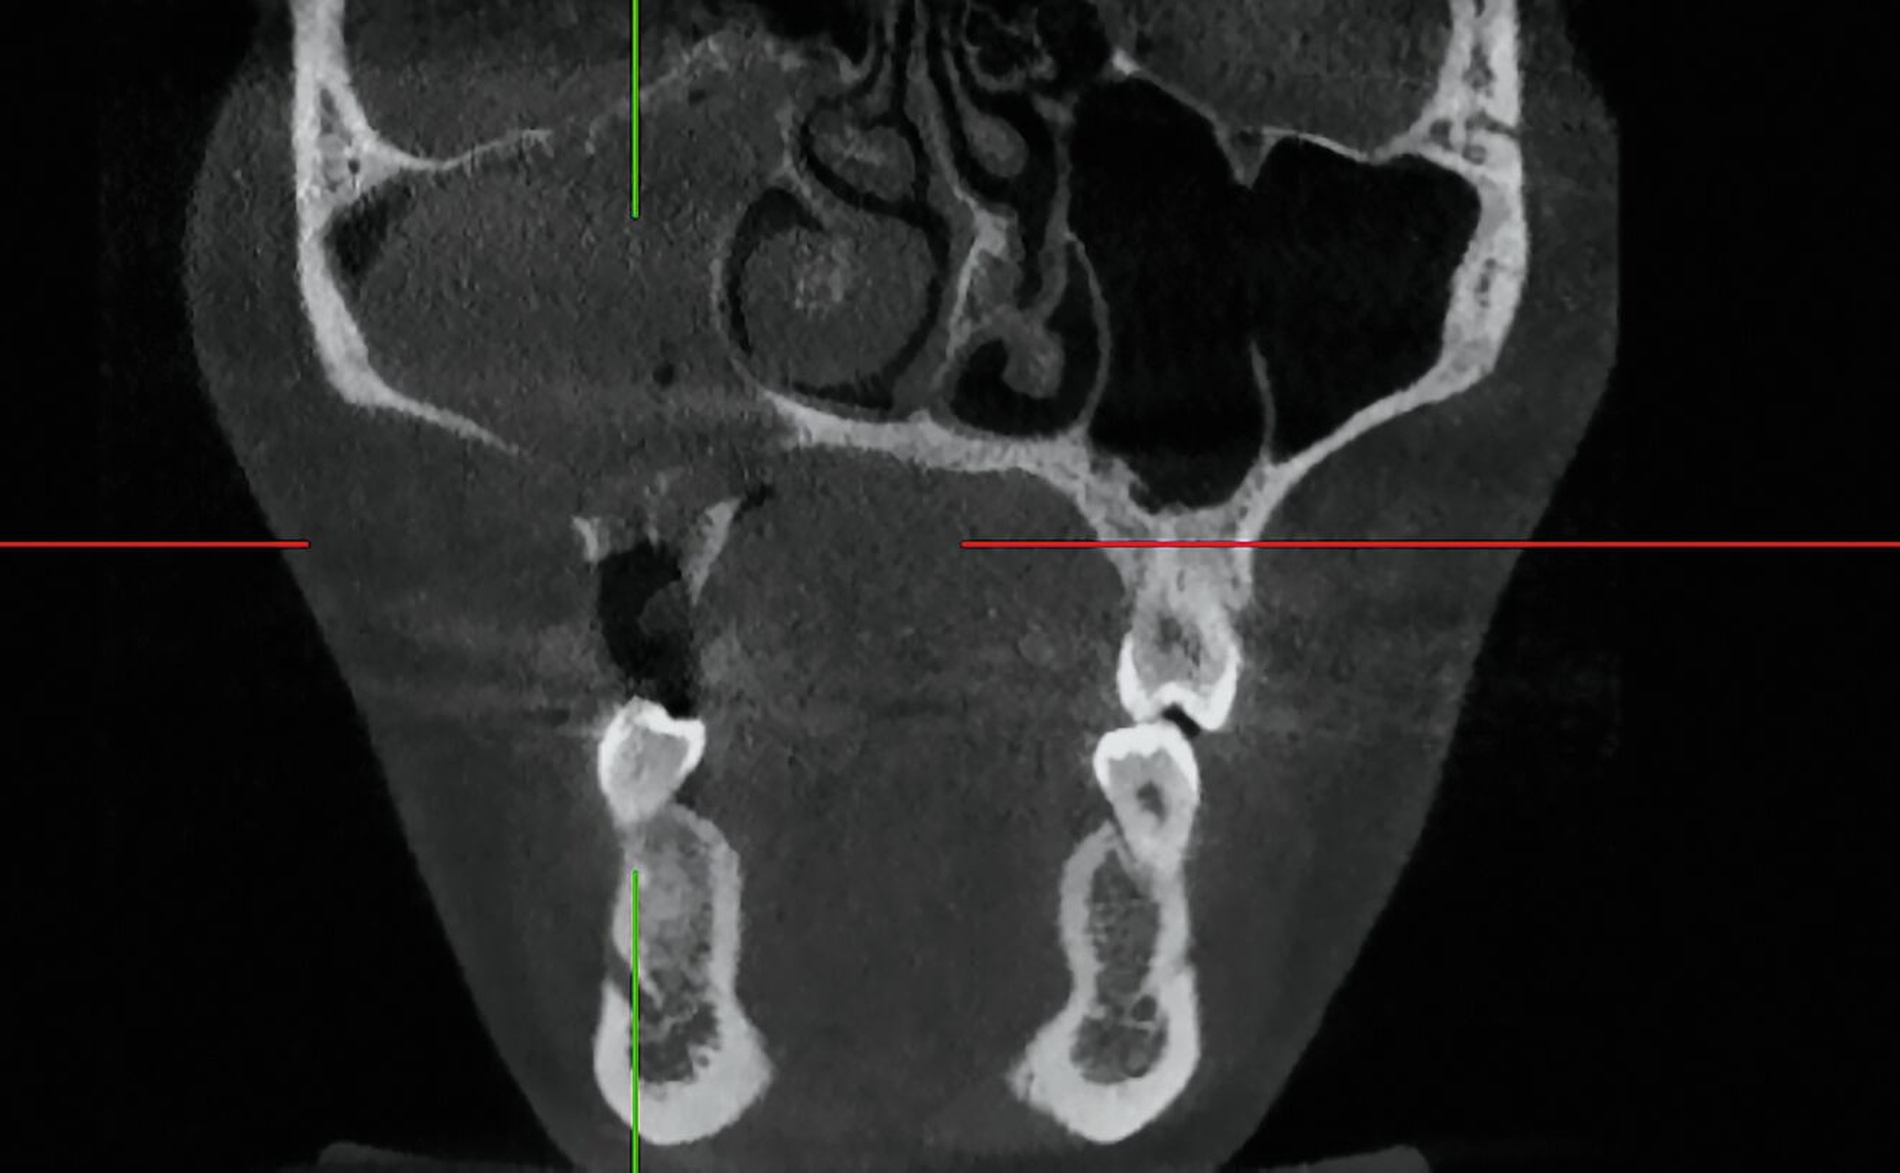

Im Verlauf der nächsten vier Wochen zeigte sich keine weitere weichgewebige Granulation (Abbildung 4). Vier Monate nach dem Spülunfall grenzte sich in der DVT-Bildgebung ein Sequester regio 15/16 ab (Abbildung 5), weshalb die Patientin nun zur operativen Sequesterotomie vorbereitet wurde. Der Sequester ließ sich zusammen mit Zahn 16 im operativen Eingriff vollständig und komplikationslos entfernen (Abbildung 6).